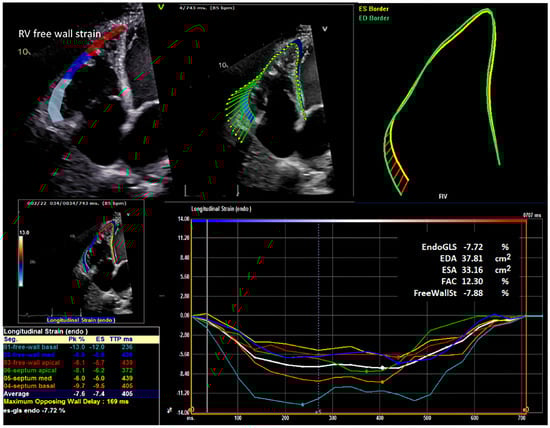

Objectives: The purpose of this study was to determine whether concomitant tricuspid valve repair (TVr) at the time of left ventricular assist device (LVAD) implantation improves outcomes in patients with ≥moderate tricuspid regurgitation (TR) and to evaluate the prognostic value of preoperative right ventricular (RV) strain. Methods: In a retrospective analysis of 100 LVAD recipients (44 TVr; 56 No-TVr), preoperative (preop) and postoperative (postop) clinical, echocardiographic, and hemodynamic variables, including pulmonary vascular resistance (PVR) and pulmonary artery pulsatility index (PAPI), were analyzed. RV free wall strain (RV-FWS) and RV fractional area change (RV-FAC) were measured by speckle tracking. Early right heart failure (RHF) was modeled with multivariable logistic regression, and 2-year mortality was assessed with Fine–Gray competing risk regression. Preoperative and three-month measurements were compared within each of the 100 patients. Results: Baseline invasive hemodynamics, RV-FWS, and RV-FAC were similar between the TVr and No-TVr groups. TVr at the time of LVAD implantation reduced postoperative TR grade, but it did not improve RV-FWS or RV-FAC at 3 months. The No-TVr patients were more often discharged home and had lower 30-day readmissions. PVR was comparable preoperatively and at 3 months postoperatively. In adjusted analyses, preop PVR, PAPI, and TVr were not independently associated with early RHF, whereas decreased preoperative RV-FWS and lower preop RV-FAC independently predicted higher 2-year mortality. Conclusions: In LVAD recipients with ≥moderate TR, concomitant TVr lowers postoperative TR severity but does not improve early RHF, RV strain-based remodeling, or 2-year mortality. Preoperative RV deformation metrics, rather than preoperative PVR or PAPI, independently predict survival following LVAD implantation with or without TVr. Full article